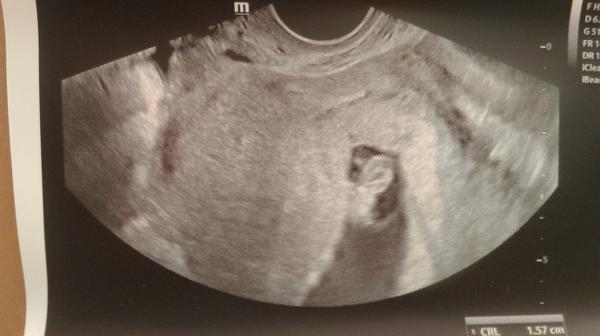

Takto sme podrastli..😍máme 1.57 cm a srdiečko bilo na celú ambulanciu 😘😍je pozadu len dva dni takže v pohode ..poradňa o mesiac 7.9 a potom mi dá tehu knižku...😍hneď mám srdiečko na mieste ...😇👌